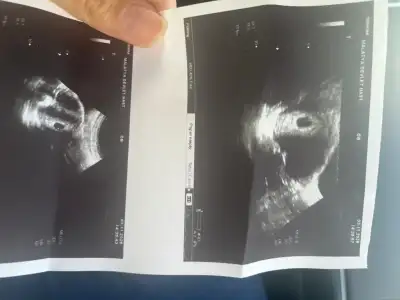

4w+5 den selamlar, iki güne bir beta takiplerinden sonra bugün Usg de keseyi gördük çok şükür.

Kızçeler 5+2 den selamlar ben de keseyi gördüm çok şükür doktor 5 mm olarak ölçtü hafta olarak 4+4 e uygun dedi 5 kutu duphaston yazdı ilk aylarda düşük olmamasını desteklemek için yazıyorum dedi. Bir de karma multivitamin yazdı Previt positive omega diye. Onun dışında 20 gün sonra da kalp atışına çağırdı inşallah onu da duyarım kese küçük olunca birazcık üzüldüm 👉🏼👈🏼

Ben de cuma günü 5+2de gördüm 6mm kese haftasıyla uyumlu dedi. Olsun inşallah sağlıkla büyürler her gün 1mm büyüyormuş galiba ☺️